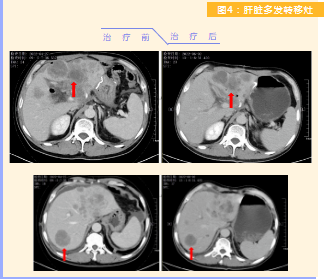

患者完成1周期治療后,上腹部疼痛癥狀基本消失,梗阻性黃疸癥狀緩解,腫瘤指標(biāo)下降(圖1),肺部多發(fā)轉(zhuǎn)移灶消失和縮?。▓D2),雙肺門(mén)淋巴結(jié)縮小(圖3),肝臟多發(fā)轉(zhuǎn)移灶縮小(圖4)。